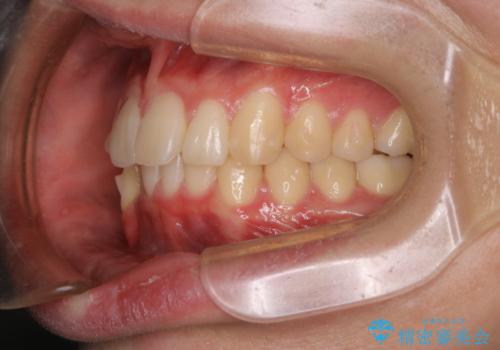

- 口元の突出感は気にならないが、上の前歯の角度と、下の前歯のがたつきが気になるとご相談にいらした方です。なるべく費用や治療期間を抑えて治療したいとのご希望に合わせて治療を計画しました。

この患者様への治療方針として、奥歯から少しずつ歯を移動させる方法と、歯をわずかに削って並べる方法とをご提案しました。短期間での治療を望まれたため、歯をサイズダウンさせて歯を並べました。わずかではあるものの、削った歯は元には戻せないことを十分ご説明し、ご理解ご了承を頂いた上で治療を行いました。